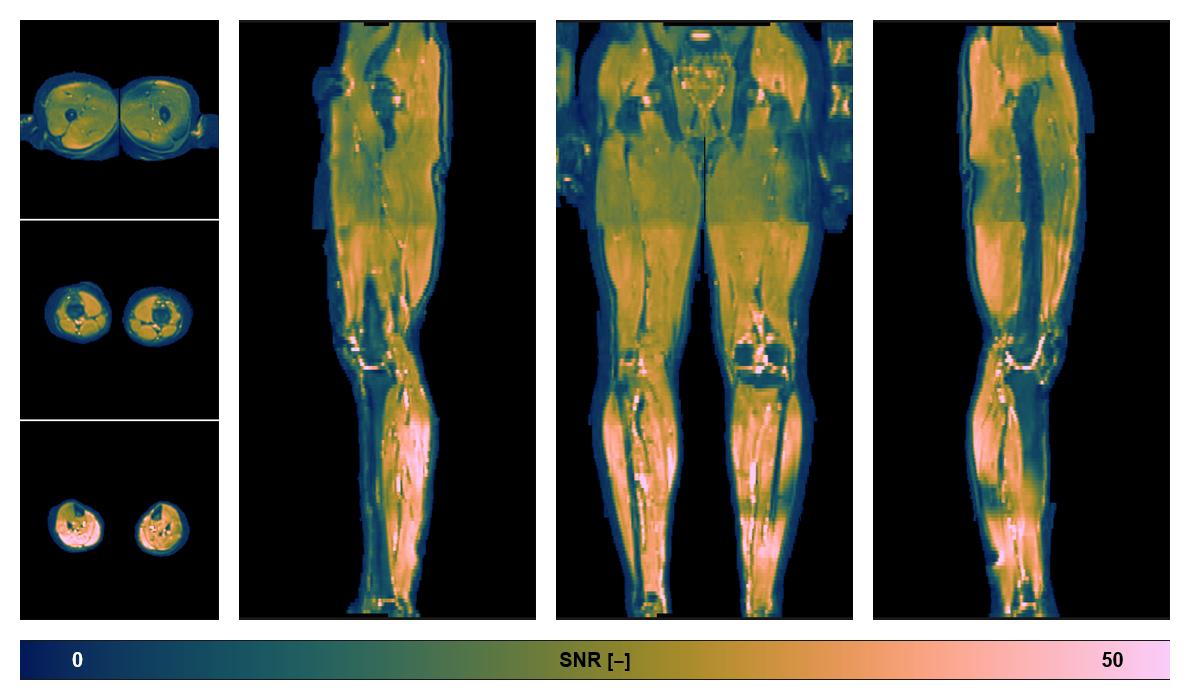

Diffusion tensor imaging

Diffusion weighted imaging with IVIM and DTI fitting to obtain muscle microstructure and muscle architecture, for information look here».

• SNR of the unweighted image

SNR distribution of the unweighted diffusion data.